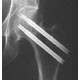

Ved skrueosteosyntese for lårhalsbrudd fant man at 16 (8 %) av 191 måtte reopereres pga. osteosyntesesvikt dersom det ble brukt 6,5 mm skruer, mot 29 (16 %) av 177 ved bruk av 4,5 mm skruer.

Operasjon for lårhalsbrudd – hyppigere osteosyntesesvikt med bruk av 4,5 mm skruer enn med 6,5 mm